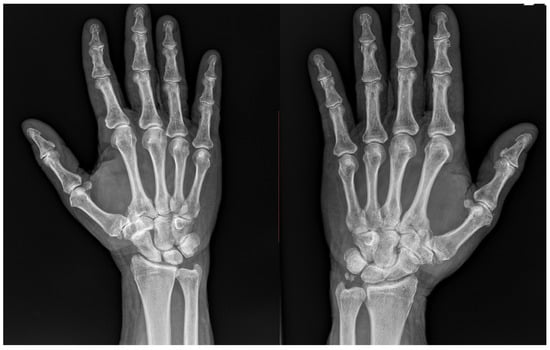

Background: Trapeziometacarpal osteoarthritis (TMC OA) is a prevalent degenerative disorder that causes considerable pain and functional limitations, especially in older individuals, whose ideal treatment is still debated in the literature. Various treatments are described to restore a good functional outcome of the thumb; over the past 50 years, biological arthroplasties have been considered the gold standard for treating advanced stages of TMC OA. However, in the last decade, the use of dual mobility cup prostheses has significantly increased, with numerous studies reporting excellent clinical outcomes. In this case report, we show the results of a patient treated on the left hand with suspension arthroplasty and on his right hand with dual mobility arthroplasty in one-stage surgery. The aim of this case report is to directly compare outcomes between trapeziometacarpal prosthesis and suspension arthroplasty performed simultaneously in the same patient. Case Presentation: The present case reports a 71-year-old male patient with bilateral TMC osteoarthritis, referred to our clinic in May 2024. His medical history included hypertension, hypertriglyceridemia, paroxysmal atrial fibrillation, and benign prostatic hyperplasia. On examination, the right hand showed grade 3 osteoarthritis according to the Eaton–Littler classification, with the trapezium maintaining adequate bone stock, making the patient eligible for trapeziometacarpal prosthesis implantation. Conversely, the left hand demonstrated scaphotrapezoid arthritis with a slight reduction in trapezial bone stock, indicating the need for trapeziectomy followed by suspension arthroplasty. Both procedures were performed during the same surgical session by the same experienced hand surgeon using a lateral approach. On the right side, the trapeziometacarpal joint surfaces were resected and replaced with a dual mobility prosthesis, while on the left side, the trapezium was excised, and suspension arthroplasty was performed using a slip of the flexor carpi radialis (FCR) tendon. Methods: The patient underwent simultaneous treatment with a dual mobility trapeziometacarpal prosthesis on the right hand and trapeziectomy with suspension arthroplasty on the left hand. Clinical outcomes (grip and pinch strength, pain, QuickDASH, satisfaction, and range of motion) were evaluated at 1, 3, 6, and 12 months. Paired comparative statistics were applied with significance set at p < 0.05. Results: At all follow-up intervals (1, 3, 6, and 12 months), the hand treated with a trapeziometacarpal prosthesis demonstrated superior grip and pinch strength compared to the hand treated with trapeziectomy and suspension arthroplasty, with the greatest difference observed at 3 months. At 12 months, grip strength increased from 28 kg to 40 kg in the prosthesis-treated hand and from 25 kg to 33 kg in the suspension arthroplasty hand. Paired comparisons were performed at each follow-up interval up to 12 months, confirming a significant difference for grip strength. Pain levels (VAS, Visual Analogue Scale) decreased progressively in both hands, with a more rapid reduction in the hand treated with a trapeziometacarpal prosthesis, reaching statistical significance. QuickDASH scores indicated an earlier return to daily activities in the hand treated with the prosthesis, although this difference was not statistically significant. Patient satisfaction was consistently higher for the hand treated with a trapeziometacarpal prosthesis, with the patient reporting a ‘very satisfied’ rating at all timepoints. Range of motion recovery, assessed through the Kapandji score and measurements of thumb abduction and extension, also favored the hand treated with the prosthesis, with statistically significant differences for abduction and extension, whereas the hand treated with trapeziectomy and suspension arthroplasty demonstrated more gradual improvement over time. Conclusions: This case highlights the functional efficacy of both surgical approaches—biological arthroplasty and trapeziometacarpal prosthesis—in the treatment of TMC osteoarthritis. Both procedures resulted in a good clinical outcome and high patient satisfaction. However, recovery was noticeably faster in the hand treated with a trapeziometacarpal prosthesis, which is consistent with findings previously reported in the literature. These observations suggest that, while both techniques are valid and effective, trapeziometacarpal prosthetic replacement may offer a quicker return to function in appropriately selected patients.

(This article belongs to the Section Hand Surgery and Research)